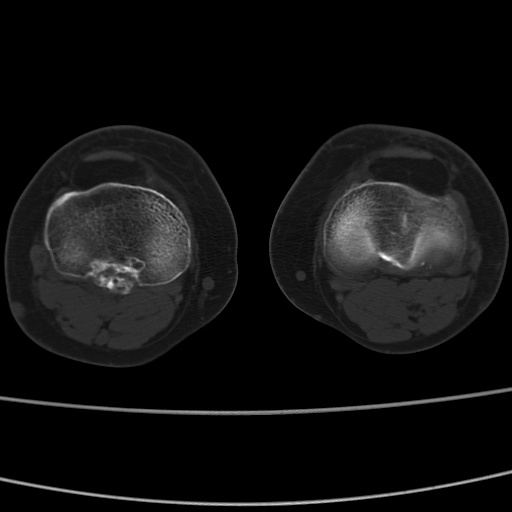

女性,50岁。【请提供患者临床症状体征】

右膝关节退行性改变,关节游离鼠。

右膝关节退行性改变,滑膜黏液囊钙/骨化并游离。